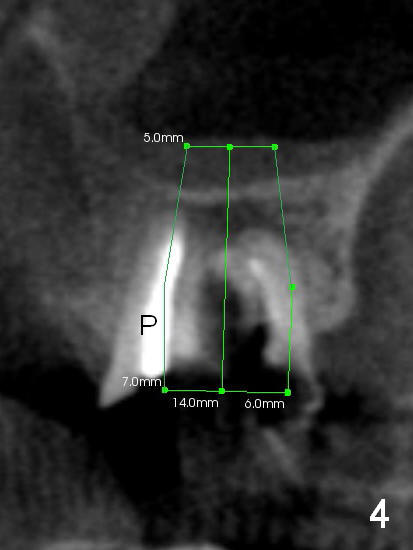

The tooth #15 of a 62-year-old man (CY) has been fractured for 4 years (Fig.1). The 3 roots (MB, DB and P) appear to be approximated each other (Fig.1,3,4) so that when the tooth is extracted (using a surgical handpiece for sectioning), the socket should be single and large. Treat the socket with Clindamycin. If the socket proves to be flat on the top, the thickness of the sinus floor is approximately 2 mm. If the bone is not so tough, use osteotomes to do sinus lift; otherwise use drills. The depth of osteotomy should be tightly monitored.

PA shows that the depth of the osteotomy is approximately 17 mm (Fig.2), whereas CT 14 mm (Fig.3,4). Intraop measurement will determine the depth.